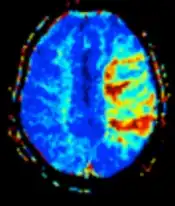

| Diffusion weighted (DWI) | Conventional | DWI | Measure of Brownian motion of water molecules.[17] | High signal within minutes of cerebral infarction (pictured).[18] |

Another application of diffusion MRI is diffusion-weighted imaging (DWI). Following an ischemic stroke, DWI is highly sensitive to the changes occurring in the lesion.[44] It is speculated that increases in restriction (barriers) to water diffusion, as a result of cytotoxic edema (cellular swelling), is responsible for the increase in signal on a DWI scan. The DWI enhancement appears within 5–10 minutes of the onset of stroke symptoms (as compared to computed tomography, which often does not detect changes of acute infarct for up to 4–6 hours) and remains for up to two weeks. Coupled with imaging of cerebral perfusion, researchers can highlight regions of "perfusion/diffusion mismatch" that may indicate regions capable of salvage by reperfusion therapy.

Perfusion weighted

Perfusion-weighted imaging (PWI) is performed by 3 main techniques:

- Dynamic susceptibility contrast (DSC): Gadolinium contrast is injected, and rapid repeated imaging (generally gradient-echo echo-planar T2 weighted) quantifies susceptibility-induced signal loss.[45]

The acquired data is then postprocessed to obtain perfusion maps with different parameters, such as BV (blood volume), BF (blood flow), MTT (mean transit time) and TTP (time to peak).

In cerebral infarction, the penumbra has decreased perfusion.[24] Another MRI sequence, diffusion-weighted MRI, estimates the amount of tissue that is already necrotic, and the combination of those sequences can therefore be used to estimate the amount of brain tissue that is salvageable by thrombolysis and/or thrombectomy.